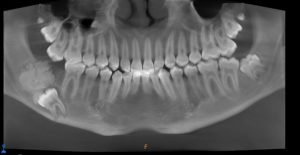

The family sought advice from several healthcare professionals who identified the rare nature of the swelling in the mouth. Since this required special treatment, Salem was eventually referred to Dr. Farzin Sarkarat, a specialist oral and maxillofacial surgeon at Medcare Dentofaces in Dubai. Concerned by the severity of the swelling in the boy’s jaw and the displacement of Salem’s right third molar tooth, Dr. Farzin conducted a thorough analysis.

“The position of the swelling was dangerously close to the inferior alveolar nerve, a critical nerve responsible for sensations in the lower teeth, chin, and lower lip. The tumor’s proximity to the nerve made the situation extremely delicate, since any oversight could result in permanent nerve damage. This made the case highly complex. From the initial evaluation, it was clear that Salem’s condition was more than a simple swelling,” explained Dr. Farzin.

“Detailed imaging and diagnostic tests revealed that Salem suffered from Ameloblastic Fibroma, a rare benign tumour originating from dental tissue that typically affects younger individuals. While non-cancerous, the tumour caused significant swelling, pain, and displacement of Salem’s teeth,” he added.

“If left untreated, the tumour could have grown larger, damaging the surrounding bones and nerves, leading to facial deformities or even loss of sensation in the jaw,” said Dr. Farzin. “We decided to perform a surgical procedure to remove the tumor, preserve the nerve, and restore Salem’s jaw.”

Dr. Farzin’s team designed a meticulous treatment plan that involved removing the tumor and impacted wisdom tooth, repositioning the nerve, and using a bone plate to reconstruct the jaw. Every step required extreme precision to avoid nerve damage and ensure Salem could regain full jaw functionality.